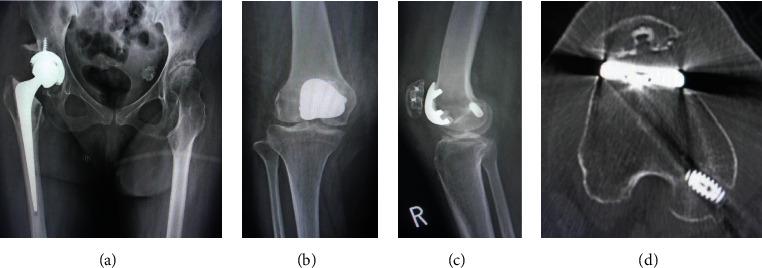

Posttraumatic patellar dislocation is rare, and consistent surgical strategy therefore has not been defined due to multifactorial factor. In this case study, we treated a case of a patellar dislocation with hip osteoarthritis and increased femoral anteversion by performing a two-staged surgery. In the first stage, total hip arthroplasty was performed, and in the second stage, simultaneous patellofemoral arthroplasty and medial patellofemoral ligament reconstruction using semitendinosus tendon autograft were performed. . A 56-year-old female patient who previously had right hip osteoarthritis complained of right knee pain after a fall. Radiographic examination showed lateral dislocation of the patella with osteoarthritic (OA) change in the patellofemoral joint and an excessive femoral anteversion with OA change on the right hip joint. Total hip arthroplasty was performed firstly to decrease femoral anteversion. Then, simultaneous patellofemoral arthroplasty and medial patellofemoral ligament reconstruction was performed for residual patellar dislocation and patellofemoral OA without tibiofemoral joint OA. At the time of the 5-year follow-up after surgery, the patient was able to walk with a wheelbarrow without any complications.

创伤后髌骨脱位较为罕见,由于多种因素,尚未确定一致的手术策略。在本病例研究中,我们通过两阶段手术治疗了一例伴有髋骨关节炎和股骨前倾角增大的髌骨脱位病例。第一阶段进行全髋关节置换术,第二阶段同时进行髌股关节置换术和使用半腱肌腱自体移植重建髌股内侧韧带。一名56岁女性患者,既往有右髋骨关节炎,跌倒后出现右膝疼痛。影像学检查显示髌骨外侧脱位,髌股关节有骨关节炎(OA)改变,右髋关节有股骨前倾角增大及OA改变。首先进行全髋关节置换术以减小股骨前倾角。然后,针对残留的髌骨脱位和髌股OA(无胫股关节OA),同时进行髌股关节置换术和髌股内侧韧带重建。术后5年随访时,患者能够使用轮椅行走,无任何并发症。